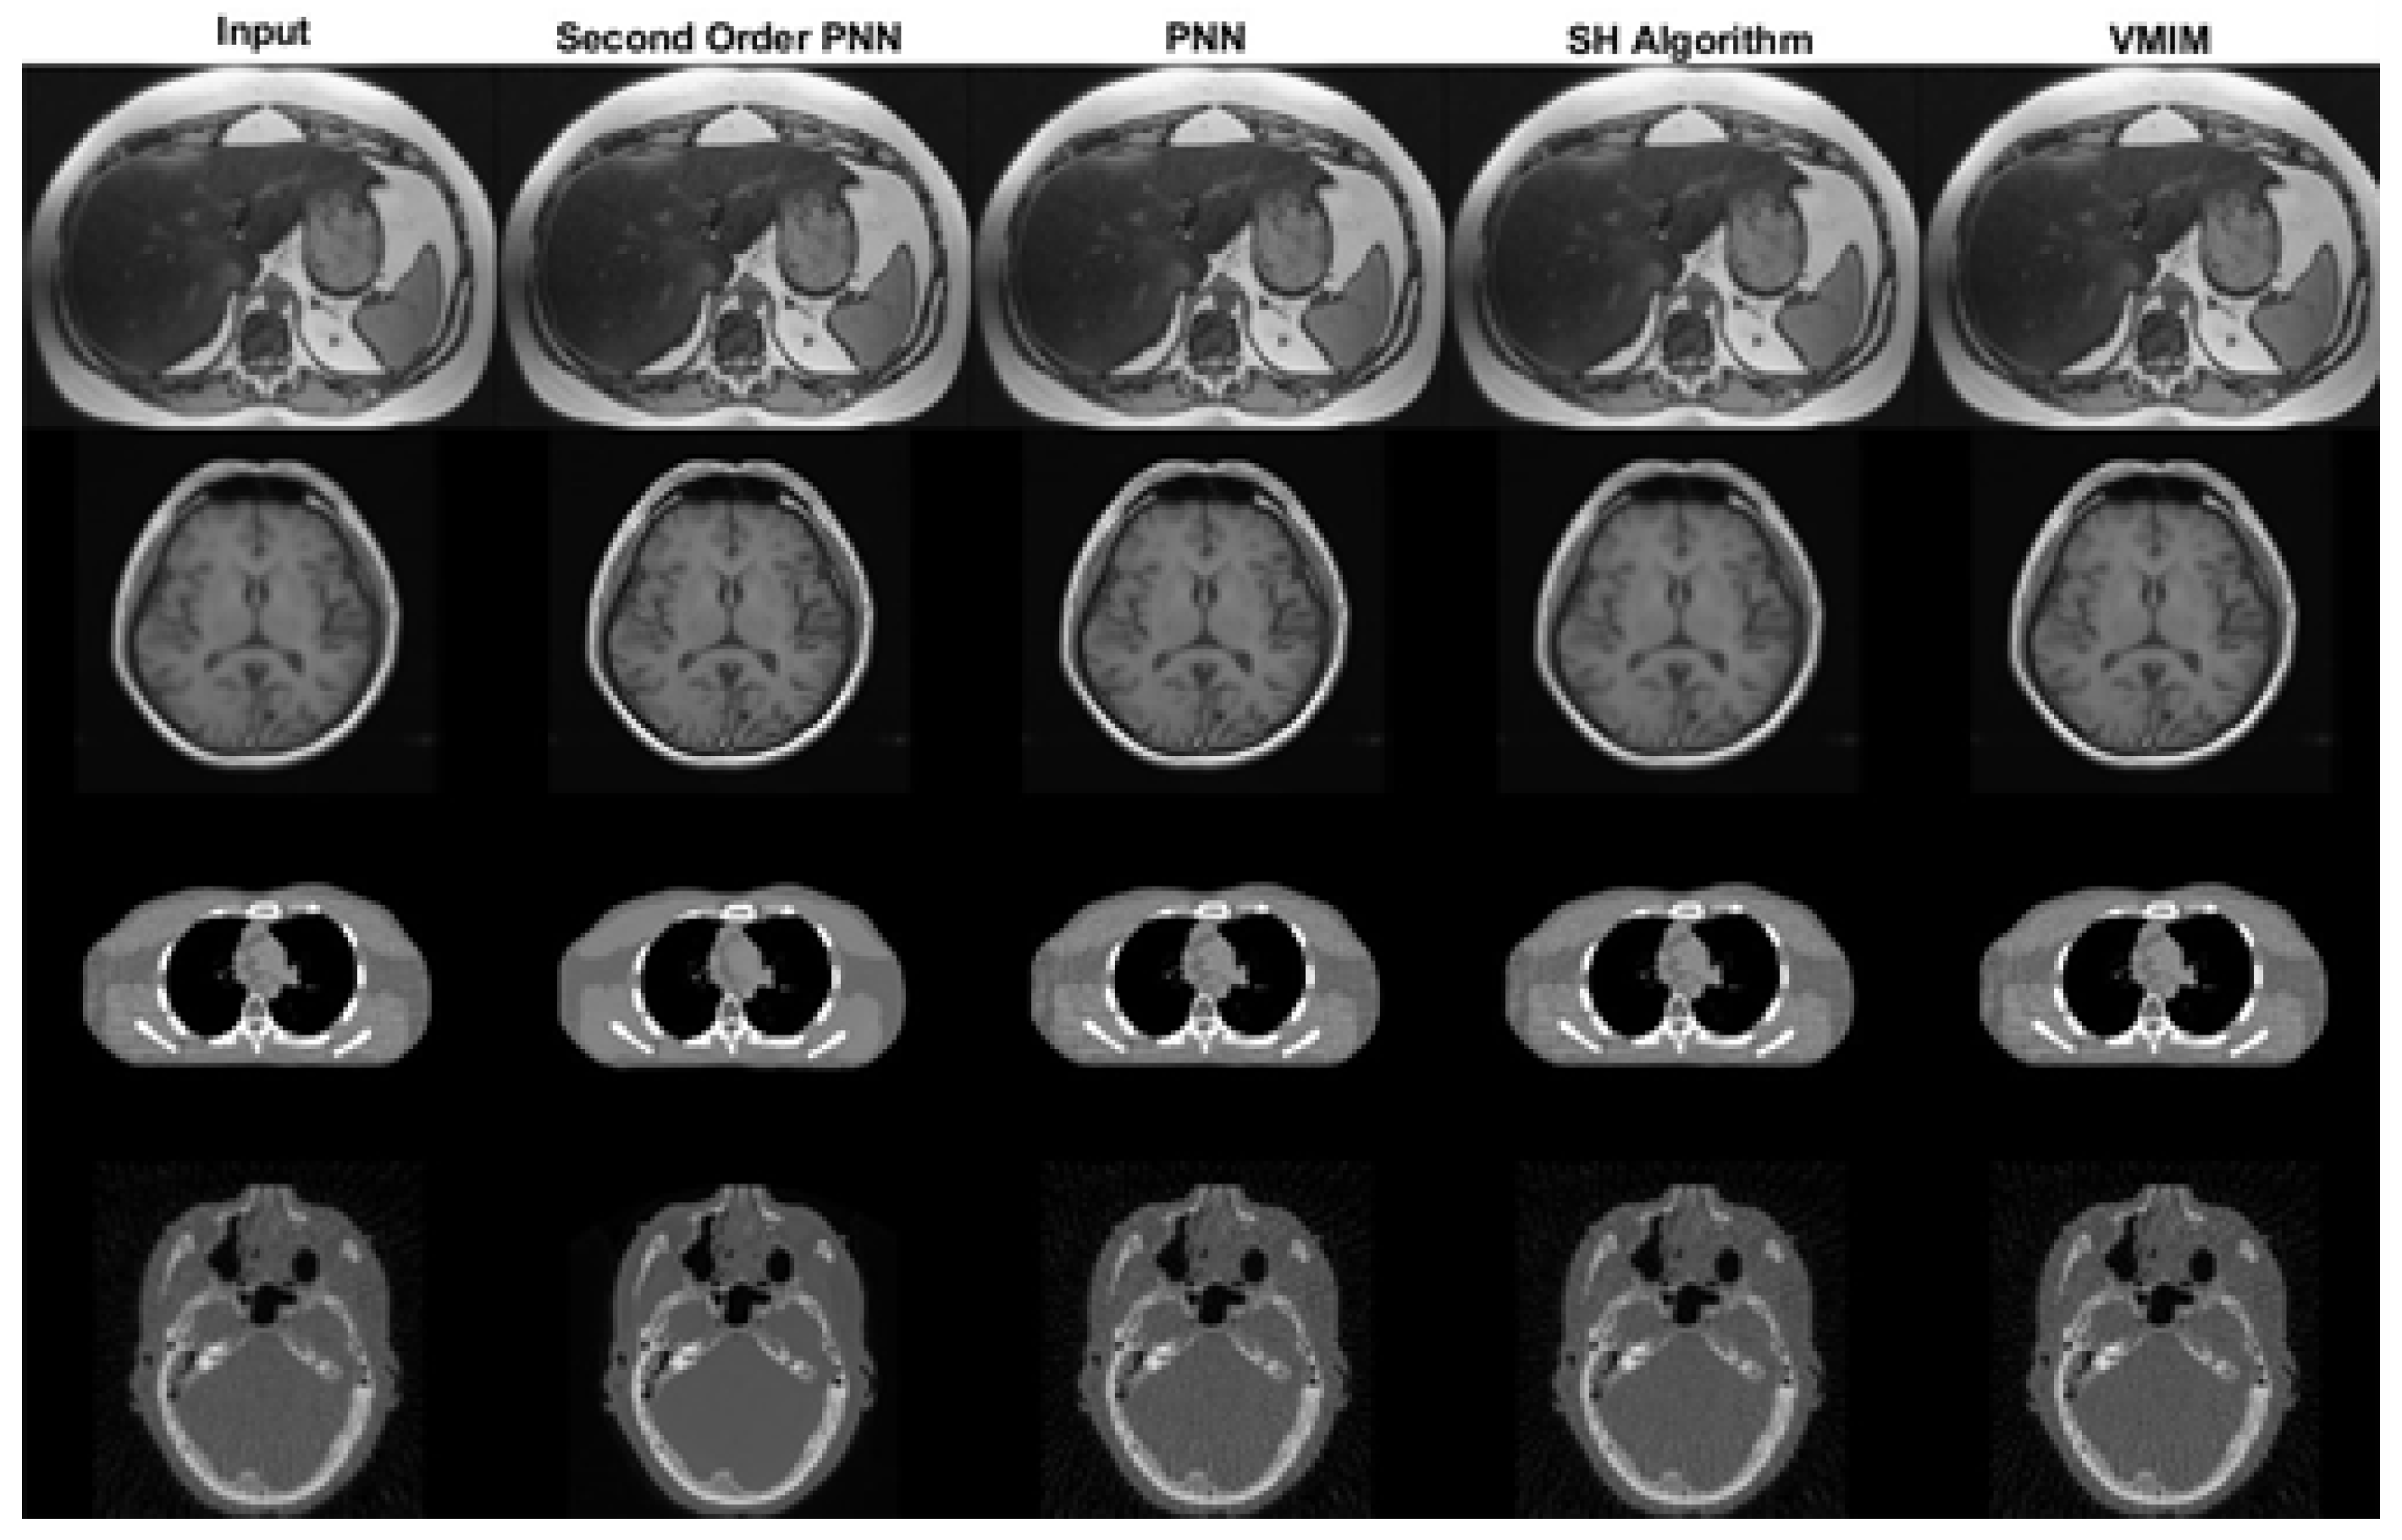

In addition to the previously reported experiments on general image restoration, we conducted further evaluations on compressed sensing reconstruction tasks frequently encountered in medical imaging. We focused on the following two specific applications:

• CS-MRI Reconstruction: We employed our method to reconstruct magnetic resonance images from compressed measurements. We compared our approach with existing CS-MRI reconstruction algorithms using publicly available datasets. The results demonstrate that our method achieves comparable or superior reconstruction accuracy as measured by metrics like SNR and SSIM.

• Sparse-View CT Reconstruction: We investigated the applicability of our method to sparse-view CT reconstruction, where a limited number of projection images is acquired. The results show that our method effectively recovers high-quality CT images despite the limited data, outperforming other methods in terms of visual quality and quantitative metrics.

Figure 7 shows the results of CS-MRI and sparse-view CT reconstruction for several samples. All samples include reference images for evaluation of the reconstruction results. Table 5 and Table 6 show the results of SSIM and SNR in this experiment, respectively. Our proposed method consistently achieved higher SSIM and SNR values compared to the benchmark algorithms across both CS-MRI and sparse-view CT reconstruction tasks. This indicates that our method produces reconstructions with the following characteristics:

• Higher Fidelity: A higher SNR value signifies a lower signal-to-noise ratio in the reconstructed image. In simpler terms, it means our method introduces less noise during the reconstruction process, leading to images that are closer to the original in terms of pixel intensity values.

• Improved Structural Similarity: A higher SSIM value implies greater structural similarity between the reconstructed image and the ground truth (original image). This metric goes beyond pixel intensity and considers factors like luminance, contrast, and structure, offering a more comprehensive evaluation of image quality.

These superior SSIM and SNR values suggest that our proposed second-order continuous-time dynamical system effectively recovers missing information and preserves structural details in the reconstructed images. While the PNN algorithm and the SH algorithm also utilize second-order methods, our approach appears to achieve a better balance between noise reduction and structural preservation, resulting in higher-fidelity reconstructions as measured by SNR and SSIM. The VMIM, despite being an iterative method, might not be as efficient in reaching the optimal solution compared to our continuous-time approach.

Figure 7. Comparison of medical images reconstructed using different algorithms. The first and second rows show CS-MRIs of the liver and brain, respectively; the third and fourth rows are sparse-view CTs of lung and brain tissue, respectively.

Mathematics 12 02360 g007

Table 5. Comparison of SSIM using four algorithms for medical images.

SSIM

Second-Order PNNPNNSH AlgorithmVMIM

Liver CS-MRI0.89590.84450.72480.7901

Brain CS-MRI0.96010.93730.87340.9109

Lung SV-CT0.99870.98510.97610.9895

Lung SV-CT0.84220.77300.73630.7912

Table 6. Comparison of the SNR of medical images recovered using the four algorithms.

SNR

Liver CS-MRI28.081526.242623.232724.7944

Brain CS-MRI32.642230.458126.527628.5781

Lung SV-CT46.856836.798934.884338.1832

Brain SV-CT30.628429.067328.450629.4119